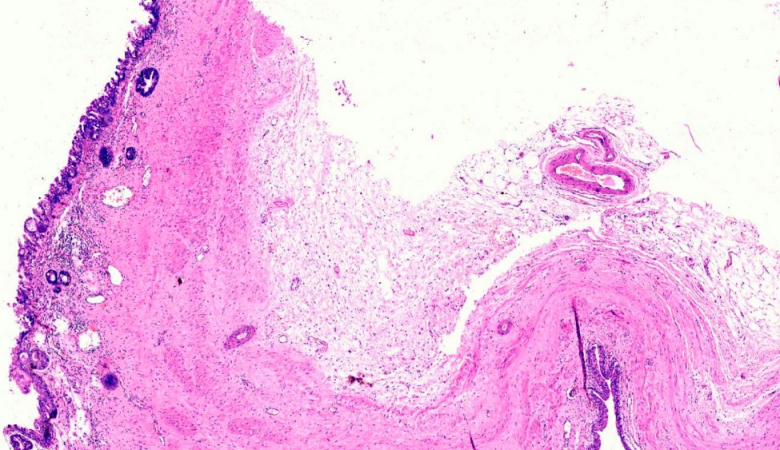

A 31-year-old male of Asian-Indian origin presented to the outpatient department with a one-year history of dull aching right-sided flank pain. There were associated symptoms of abdominal distension and difficulty in voiding urine for the same duration. There was no history of polyuria, graveluria, hematuria or dysuria. On examination, right costovertebral angle tenderness was noted. General and systemic examinations were unremarkable. No lymphadenopathy was noted. On investigation, complete blood count and liver and renal function tests were within normal limits. Urine microscopy showed increased pus cells (20–30/high power field); there were no red blood cells, casts, crystals or malignant cells. Ultrasonography of kidney, ureter and bladder region revealed right-sided hydronephrosis. Computed tomography (CT) scan revealed a hyperdense mass of 2.3x4.6 mm in the right renal pelvis with severe hydronephrosis and cortical thinning (Figure 1 [Fig. 1]). Renal dynamic scan revealed a poorly functioning right-sided kidney. Considering the poor functional status, right-sided nephrectomy was performed and the specimen was sent for histopathological examination. On gross examination, the kidney measured 11x8x5 cm with a cut surface showing dilated pelvicalyceal system filled with slimy watery fluid; the renal pelvis was thickened with a greyish-white cut surface. Multiple stones were noted in the pelvis and kidney parenchyma. Microscopic examination revealed features of chronic pyelonephritis; the adjacent renal pelvis showed pseudostratified columnar epithelial metaplasia with presence of tumor cells arranged in the form of glands and suspended in mucin pools. The tumor infiltrated lamina propria and superficial layers of the muscle coat of the renal pelvis (Figure 2 [Fig. 2], Figure 3 [Fig. 3], Figure 4 [Fig. 4], Figure 5 [Fig. 5]). Adenocarcinoma in situ was noted in the adjacent ureter (Figure 6 [Fig. 6]). Pathological TNM staging was pT2aNxMx.

Figure 3: Mucinous adenocarcinoma involving the renal pelvis (H&E, 200x)

Figure 4: Tumor infiltrating the lamina propria and superficial layers of muscularis propria (H&E stain, 400X)

Figure 5: Showing transition of normal transitional epithelial lining to malignant columnar lining (H&E stain, 400X)

Figure 6: Adenocarcinoma in situ involving the ureter (H&E stain, 200X)